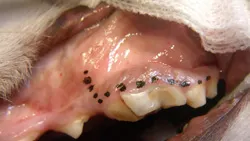

A full thickness mucoperiosteal gingival flap is planned (indicated by the dotted line). Important surgical anatomy includes the parotid and zygomatic salivary ducts at the distal (caudal) aspect of the affected tooth and the infraorbital neurovascular bundle, which is mesial (rostral) to the vertical incision location.